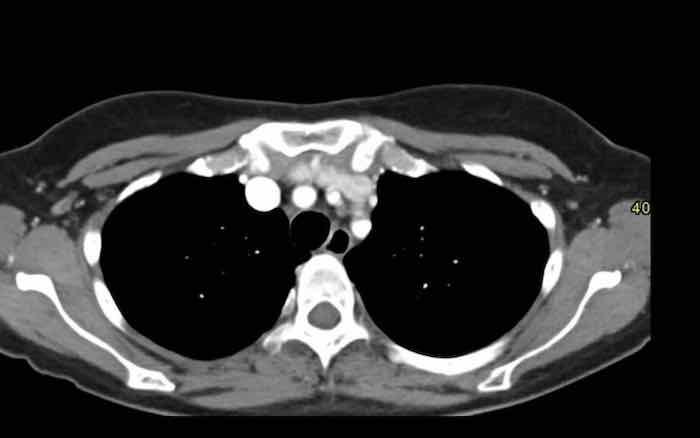

Các hình ảnh này của một nam giới 19 tuổi, được chụp CT để loại trừ thuyên tắc phổi.

Phát hiện tình cờ một khối ở khoang trước mạch máu.

Chẩn đoán có khả năng nhất là tăng sản tuyến ức và MRI được thực hiện để phân biệt thêm khối này.